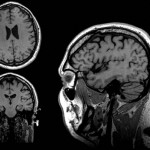

Resonancia magnética Aplicaciones en Neurología. RM Neuro, En la actualidad La resonancia magnética es una técnica de imagen indispensable para el correcto diagnóstico de algunas patologías. Proporciona imágenes detalladas de los tejidos del cerebro y los nervios, al igual que imágenes claras de partes del cerebro que son difíciles de visualizar con claridad en tomografías computarizadas.

Resonancia magnética Aplicaciones en Neurología. RM Neuro, En la actualidad La resonancia magnética es una técnica de imagen indispensable para el correcto diagnóstico de algunas patologías. Proporciona imágenes detalladas de los tejidos del cerebro y los nervios, al igual que imágenes claras de partes del cerebro que son difíciles de visualizar con claridad en tomografías computarizadas.

Nuestra totalmente nueva resonancia magnética digital es una plataforma de 1.5T diseñada para ayudarle a mejorar la productividad de la adquisición de imágenes y reducir el tiempo que tarda el estudio. Con una calidad de imagen insuperable y una gama de aplicaciones muy útiles según la especialidad y el tipo de paciente.